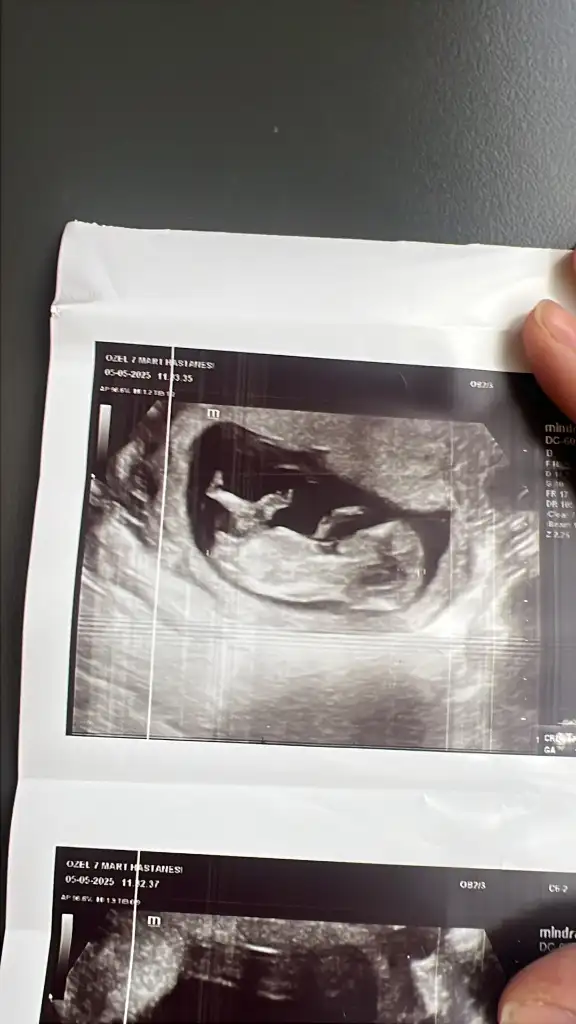

Canım erkeğe benziyor belli mi simdi cinsiyeti ne zaman belli olacakMerhaba kızlar cinsiyet tahmini yapabilen var mı acaba 13 haftalık ikiz gebelik birinin cinsiyeti öğrendik ama bu miniginkini doktorumuz daha var dedi. Tahminleri alayım? Eki Görüntüle 3582600

Bu belli oldu canım evet erkek ama bir tane daha var onun belli değil cinsiyeti şu bak sence bu neCanım erkeğe benziyor belli mi simdi cinsiyeti ne zaman belli olacak

Alttaki erkek üstteki kız gibi geldi banaMerhaba kızlar cinsiyet tahmini yapabilen var mı acaba 13 haftalık ikiz gebelik birinin cinsiyeti öğrendik ama bu miniginkini doktorumuz daha var dedi. Tahminleri alayım? Eki Görüntüle 3582600